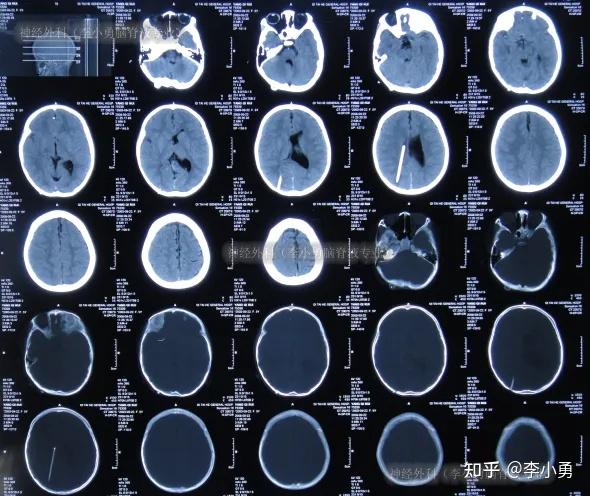

后枕小脑脊膜膨出术后仍脑积水,脑分流术后颅内感染性顽固头痛性昏迷